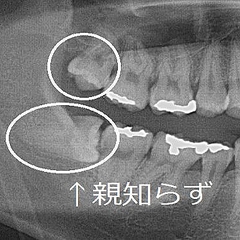

完全に埋まっている 親知らず(完全埋伏)について 完全に骨の中に親知らずが埋まっている場合を、歯科専門用語で完全埋伏と呼びます。完全に骨の中に親知らずが埋まっていますので、親知らずを抜歯するには、骨を削る必要があります。 完全に埋まっている親知らずの状態 抜歯をしない · 親知らずが成長し始めて、少し奥の歯肉が少し盛り上がっているけど、今のところ痛みや腫れといった症状はないからといって、放置していませんか? そのまま成長を続けると、トラブルを招く危険性があります。多くの人が親知らずの抜歯を何故、親知らずを抜歯するの? 症例1 のような、手前の歯の歯根が溶けてしまうという症例は滅多にありませんが、稀に見受けられます。 炎症組織である不良肉芽は、多くの方に見られます。 また、菌がいるということは、その中には虫歯菌も存在する

親知らず 横向き 埋まってる 放置- · なぜ放置しておくと問題なのか 親知らずは、一番奥に生える歯です。斜めや横向きに生えていると、歯ブラシが届きにくく汚れが溜まりやすいので、 周囲の粘膜が腫れたり、痛くなったりすることがありむし歯や歯周病になりやすい状態になります。 · 親知らずの種類と、生え方によるリスク 親知らずの生え方には4つのタイプがあり、 『まっすぐに生えてくるタイプ』『横向き、または斜めに生えてくるタイプ』『骨の中に埋まっているタイプ』『逆向きに生えているタイプ』 に分けられます。